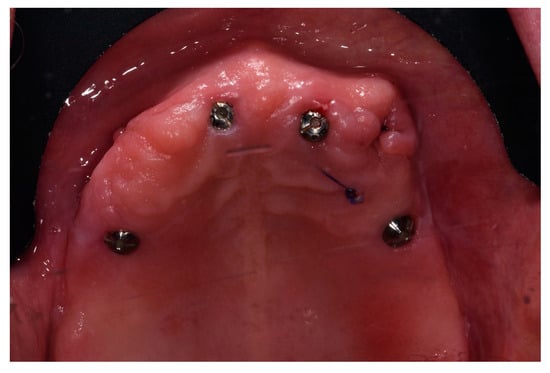

2.2. Surgical Procedures and Post-Operative Care